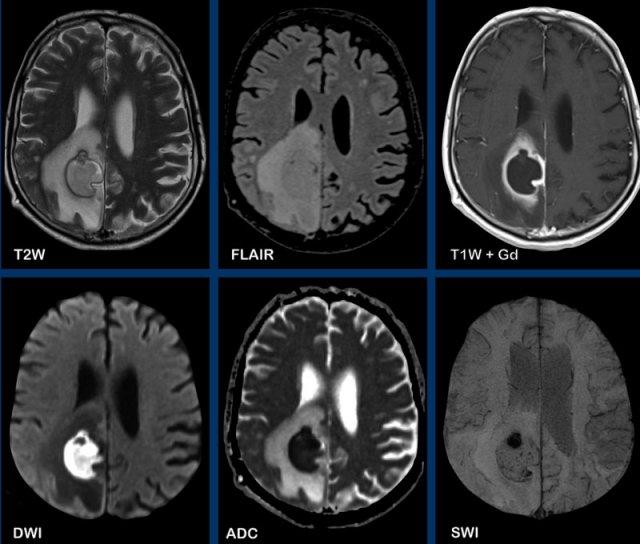

Toxoplasmosis

Các hình ảnh này của bệnh nhân nữ 50 tuổi, nhập viện với triệu chứng liệt nửa người bên trái.

Tiền sử bệnh không có gì đặc biệt.

Hình ảnh

Ghi nhận một tổn thương ngấm thuốc dạng viền ở thùy trán phải.

Không có hạn chế khuếch tán ở trung tâm, nhưng có dấu hiệu bia lệch tâm (eccentric target sign).

Dấu hiệu bia này gợi ý mạnh cho chẩn đoán toxoplasmosis não.

Dấu hiệu này được cho là biểu hiện của các mạch máu viêm ngấm thuốc nằm bên trong khoang áp xe.

Đây là trường hợp tương tự của bệnh nhân nữ 34 tuổi, nhập viện với triệu chứng động kinh.

Ghi nhận một tổn thương ngấm thuốc dạng viền ở thùy trán trái với dấu hiệu bia và hạn chế khuếch tán dạng viền.

Lưu ý thêm giảm tín hiệu trên chuỗi xung T2W và FLAIR.

Chẩn đoán cuối cùng: toxoplasmosis.

Trong khi các tác nhân vi khuẩn gây áp xe điển hình thường gây hạn chế khuếch tán ở trung tâm, các tác nhân không điển hình như nấm và toxoplasmosis thì không, khiến chẩn đoán áp xe não trở nên khó khăn hơn.

Dấu hiệu bia lệch tâm như trong trường hợp này rất có giá trị cho chẩn đoán.